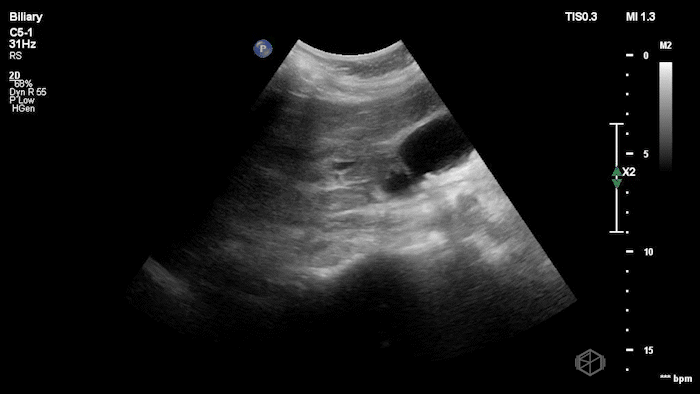

08 - What are the 6 signs of cholecystitis and what signs are visible here?

6 signs of cholecystitis — aGBW thickening >4mm, gallbladder wall edema, stone-in-neck (SIN) sign, pericholecystic fluid, hydropic gallbladder 10cm x 5cm, sonographic Murphy’s

Signs visible on this scan — SIN, hydropic gallbladder, gallbladder wall thickening

08A - The same patient above - what is the next procedure this patient needs and why?

ERCP - choledocholithiasis - stone present in bile duct.